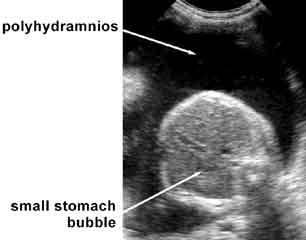

What is the sonographic appearance of esophageal atresia?

polyhydramnios

stomach usually not identified